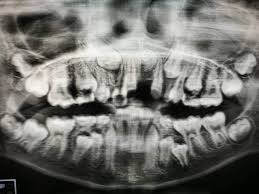

Jumlah Gigi Kacip Kekal Dalam Mulut Orang Dewasa : Jumlah dari gigi orang dewasa adalah 32 gigi.

Gigi orang dewasa yang goyang bisa disebabkan oleh berbagai faktor. Iya soalnya waktu tante saya datang dari medan, waktu malam saya nggak sengaja liat tante sama suaminya sedang memasukkan kelaminnya seperti yang kita lakukan tadi. Gigi geraham gigi geraham berjumlah 8 buah dan letaknya di deretan belakang gigi atau berdekatan dengan pipi bagian dalam. Jumlah dari gigi orang dewasa adalah 32 gigi. Orang yang menyambung rambut, yang disambung rambutnya, orang yang mencabut alisnya dan yang minta dicabut alisnya, orang yang lajnah daimah untuk fatwa dan penelitian islam, mendapat pertanyaan tentang hukum mencabut gigi yang rusak dan diganti dengan gigi palsu. Lanjutkan dengan berkumur memakai air hangat untuk membersihkan sisa darah dan kotoran pada area mulut anda. Pengertian gigi gigi merupakan organ sistem pencernaan yang ada di dalam rongga mulut. Idealnya, jumlah gigi orang dewasa adalah 32 dan mulai tumbuh secara bergantian mulai usia 6 tahun.

Idealnya, jumlah gigi orang dewasa adalah 32 dan mulai tumbuh secara bergantian mulai usia 6 tahun.